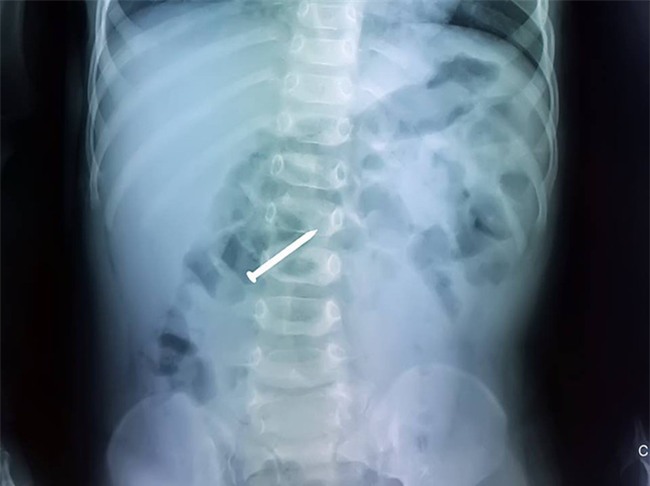

Bé C.P. (21 tháng tuổi, ngụ huyện Củ Chi, TP.HCM) được gia đình đưa đến một bệnh viện ở địa phương trong tình trạng đau bụng. Khi chụp phim, các bác sĩ phát hiện một chiếc đinh nằm ở khung tá tràng của đứa bé.

Sau

khi hội chẩn nhanh giữa các chuyên khoa, bệnh nhi được chuyển ngay đến

phòng mổ. Các bác sĩ tiến hành gây mê và làm thủ thuật nội soi thực quản

- dạ dày - tá tràng để lấy dị vật. Sau nội soi, cây đinh dài 3cm được

lấy an toàn ra ngoài. Hiện tại bé đã khỏe mạnh, chơi đùa bình thường và

được theo dõi tại nhà.